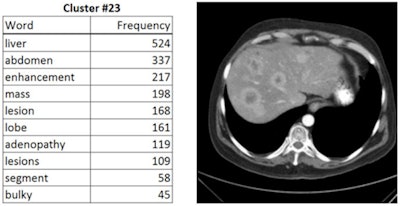

"We're developing ways to use our entire PACS collection of radiology images to develop all-in-one abdominal automated image interpretation software," he wrote in an email. "To achieve our goal, we're using the radiology reports as labels to teach deep-learning computer software to detect and assess disease in the abdomen. In this way, we don't need to manually annotate millions of radiology images. Progress is very rapid, but it is difficult to predict how long it will take for such software to mature."